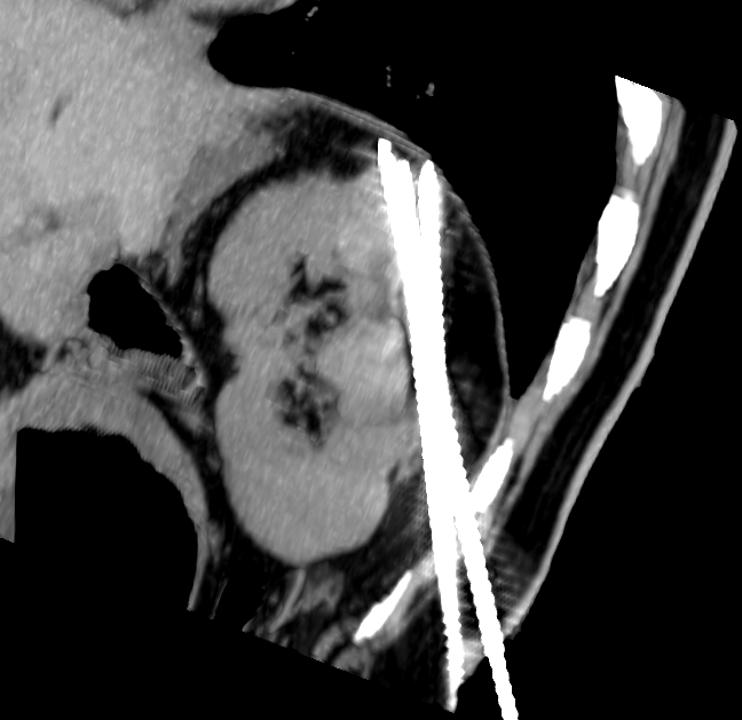

Stent placement is a suboptimal mechanical solution to chronic venous disease. We are doing translational research using a sheep model to study potential gene therapy strategies to minimize post-thrombotic venous changes and ameliorate the downstream quality-of-life complications.

- Reference: Li, N., Ferracane, J., Andeen, N., Lewis, S., Woltjer, R., Rugonyi, S., Jahangiri, Y., Uchida, B., Farsad, K., Kaufman, J.A. and Al-Hakim, R.A., 2022. Endovascular Venous Stenosis and Thrombosis Large Animal Model: Angiographic, Histological, and Biomechanical Characterizations. Journal of vascular and interventional radiology: JVIR, 33(3), pp.255-261. https://doi.org/10.1016/j.jvir.2021.10.036